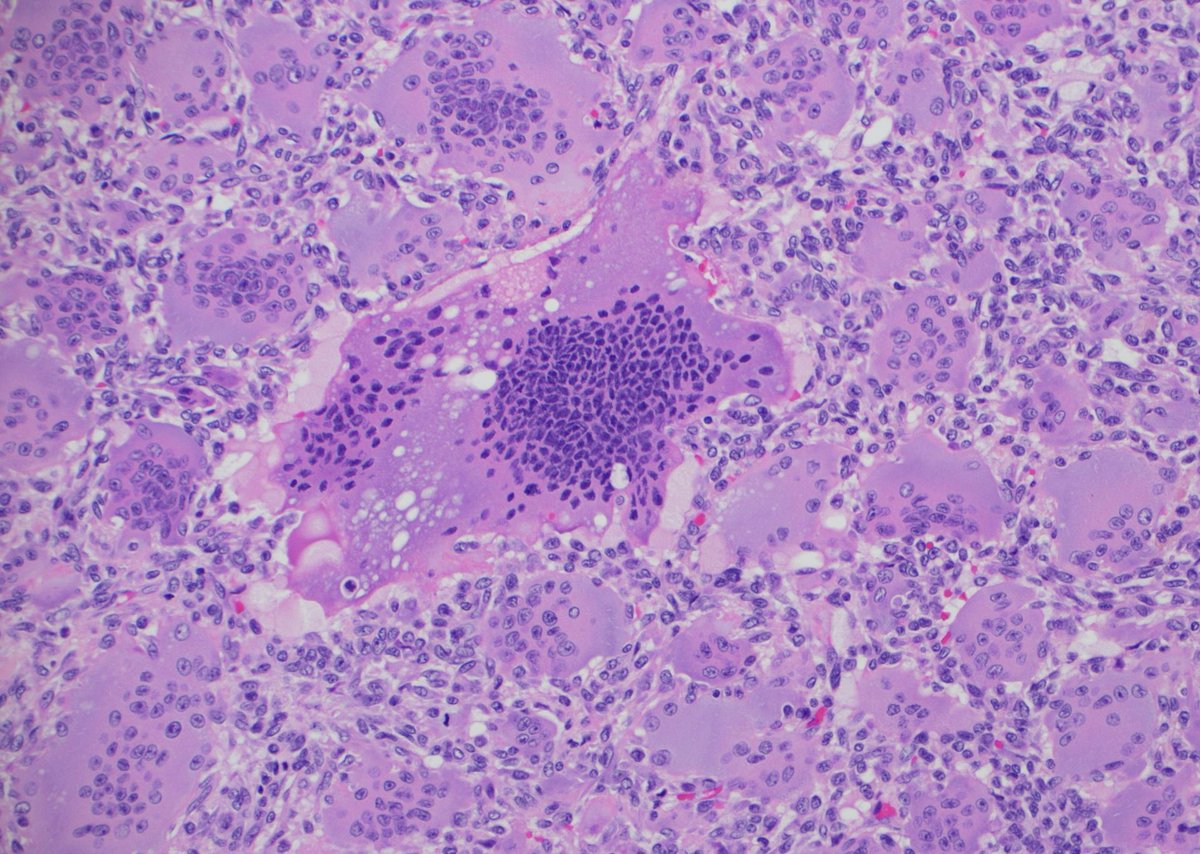

A #pathology classic! Touch prep and H&E section. What's your diagnosis? Answer ✅ youtu.be/yB24r0iAWDs?si… #Pathology #dermpath #dermatology #dermatologia #dermtwitter #BSTpath

A #pathology classic! Touch prep and H&E section. What's your diagnosis?